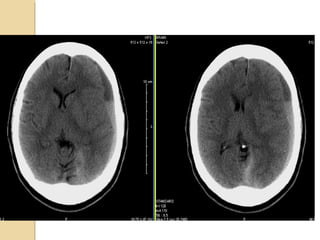

SUBDURAL HEMATOMASUBDURAL HEMATOMA Occursbetween the dura and arachnoid Can cross the sutures but not the dural reflections Due to disruption of the bridging cortical veins Hypodense(hyperacute, chronic), isodense(subacute), hyperdense(acute)

• 12.